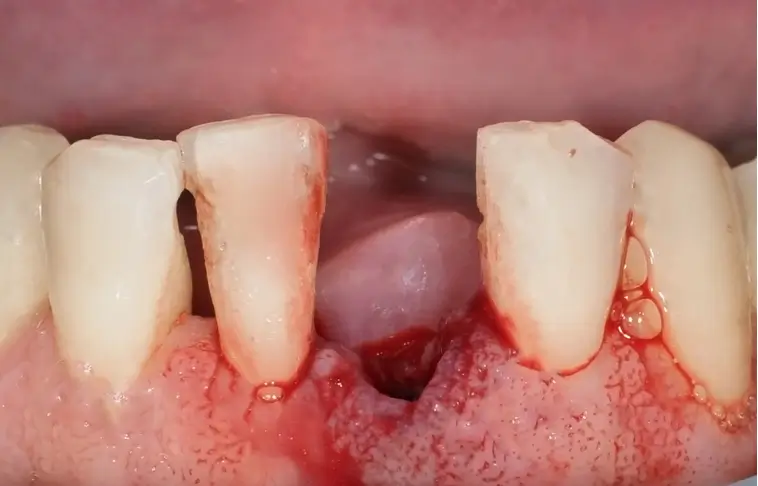

Do your gums bleed when you brush or floss?

That’s not “normal.” It’s the earliest sign of a hidden disease silently spreading inside your mouth.

The Silent Epidemic in Your Gums… And the Breakthrough Dentists Ignore

Nearly 47% of adults over 30 have gum disease, and 1 in 3 suffer from bad breath. Dentists see it every day—yet they keep telling you to “brush more and rinse harder.”